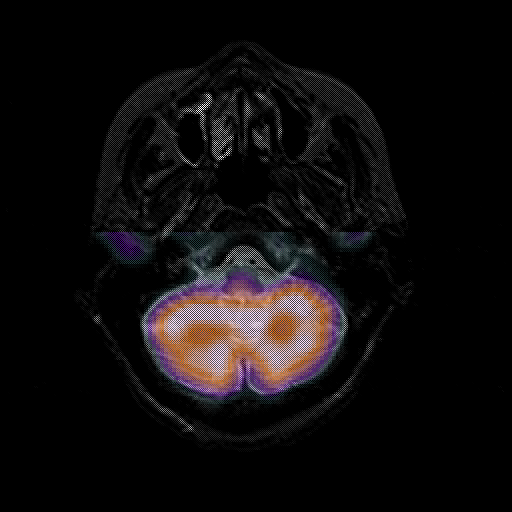

overlay 1: Slice 10

Slice 10